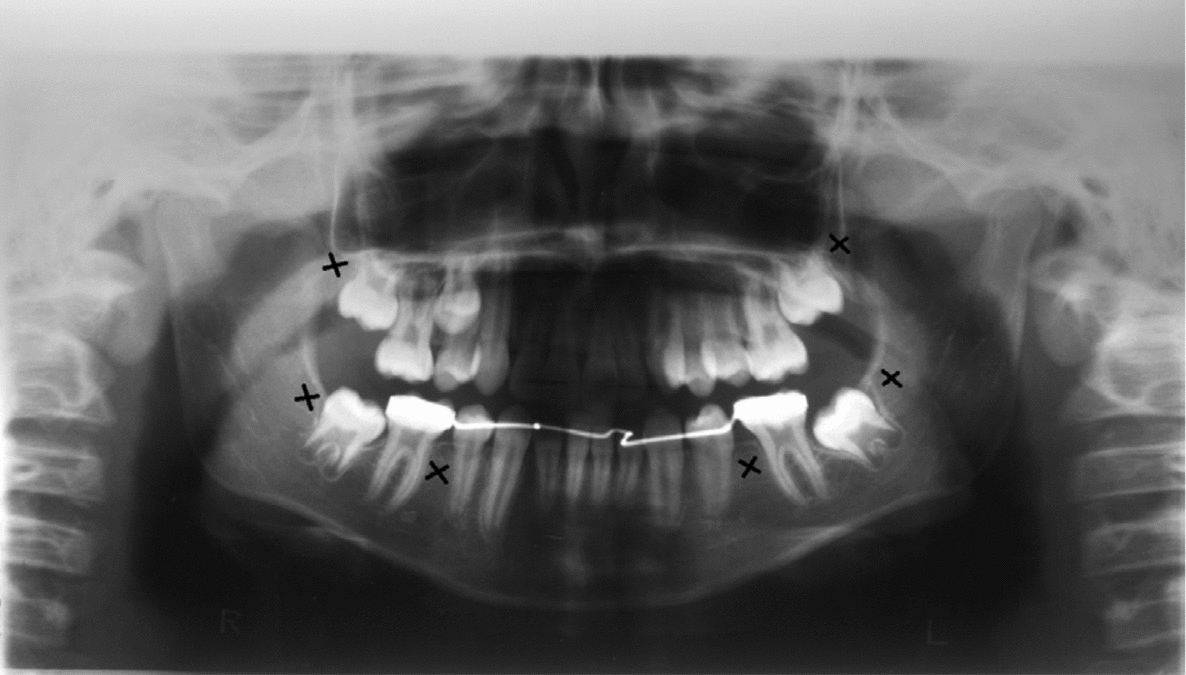

Clinical and radiographic tests revealed that patients 1 and 2 had tooth agenesis, and excluded other causes for the missing teeth, such as dental caries, periodontal disease, or aggressive trauma. Patient 1 had a congenital absence of lower second premolars and upper and lower third molars (Figure 1). In contrast, patient 2 revealed agenesis of upper and lower second premolars, as well as that of upper and lower third molars (Figure 2). Their father also had unilateral agenesis of a lower permanent incisor (data not shown).

FIGURE 2 Panoramic radiograph of patient 2 teeth in 2011; those missing are indicated with an x.